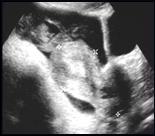

Right adnexal pain, no fever or wbc

Ruptured Hemorrhagic Cyst